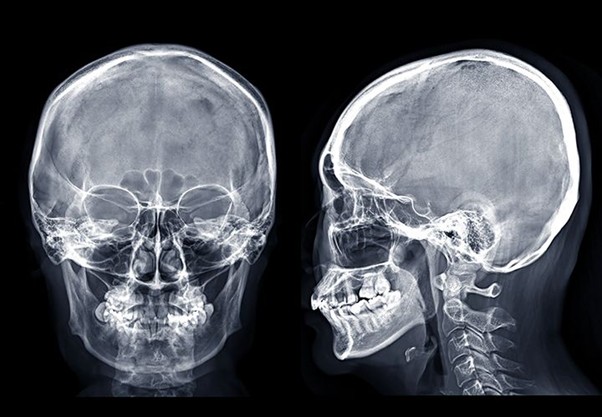

La telerradiografía o radiografía del cráneo, es una técnica radiográfica extra-bucal mediante la cual se obtienen unas imágenes muy nítidas de los dientes y huesos de la cara del paciente. La telerradiografía permite un estudio del crecimiento facial del paciente y una valoración de las estructuras maxilares, mandibulares y sus relaciones con las bases craneales. Se caracteriza por ser tomada a cierta distancia del paciente.

Telerradiografía lateral

Se solicita como examen complementario en estudio de ortodoncia, cirugías bucal y en el diagnóstico de las especialidades de ortodoncia, cirugía maxilofacial y prótesis, proporcionando registros antes y después del tratamiento. También para observar datos de un traumatismo, enfermedades o anomalías del desarrollo, para evaluar el crecimiento y el desarrollo facial. O bien para realizar una cefalometría y analizar la anatomía cráneo-facial, diferenciar las anomalías óseas y dento-alveolares, analizar las relaciones dentales y las vías aéreas y tejidos blandos.

Telerradiografía frontal

Sirve para obtener una imagen frontal de las estructuras de interés a nivel craneal, para el estudio de asimetrías faciales y desviaciones de la línea media. Las técnicas frontales más utilizadas son aquellas que permiten observar, fundamentalmente, los senos maxilares.